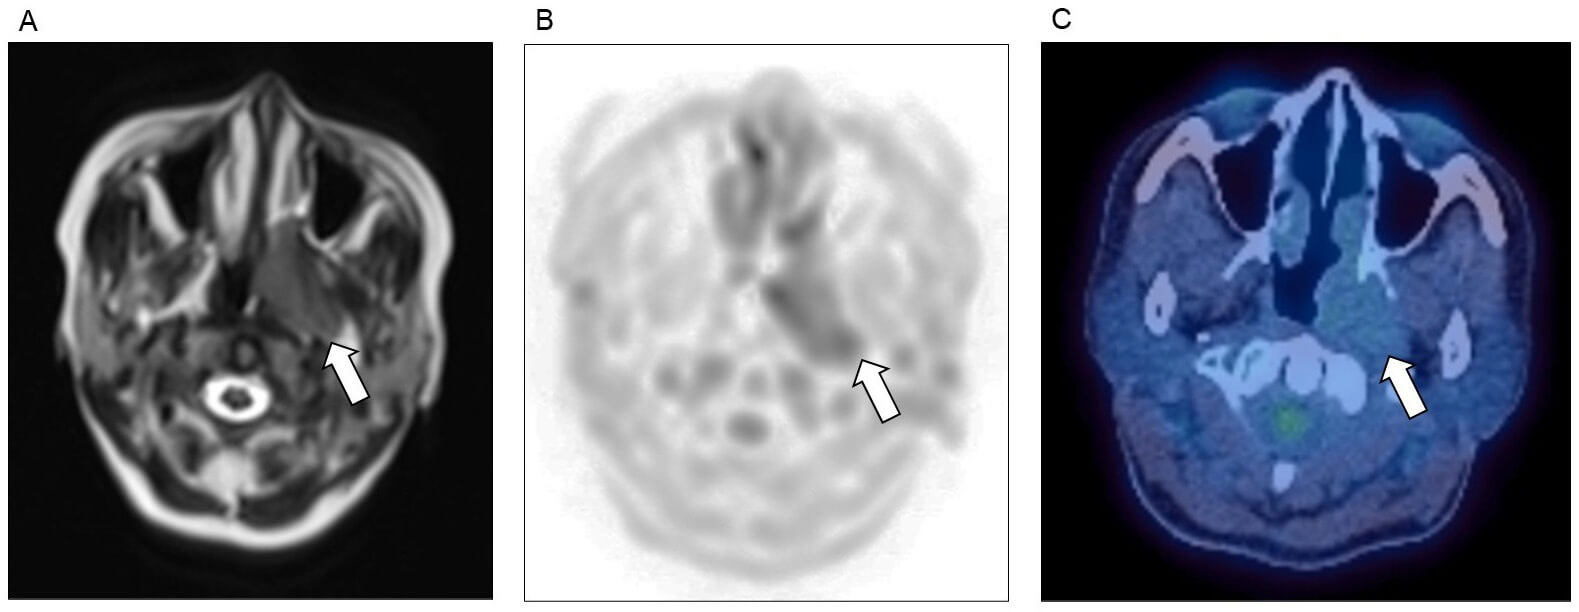

Solitary plasmacytoma is an isolated tumour of plasma cells which can be either in association with bone marrow, or entirely outside of the bone marrow (extramedullary), but by definition, with no evidence of myeloma elsewhere. Extramedullary plasmacytomas can occur anywhere, but most commonly in head and neck (Fig. 3). Both solitary bone and extramedullary plasmacytomas are treated with radiotherapy or surgical resection, however most patients will later develop myeloma, with the highest risk amongst those with bone plasmacytomas [48, 49] (Fig. 4). Plasmacytomas may or may not be associated with a monoclonal immunoglobulin protein and imaging is always key for detection of relapse.

Fig. 3.

Plasmacytoma affecting the head and neck. Nasopharyngeal plasmacytoma (arrows), as detected on (A) MRI T2 sequence, (B) MRI diffusion weighted imaging (DWI), and (C) FDG-PET/CT imaging.